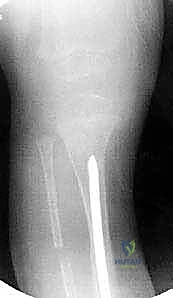

الخطوة الرابعة: تجهيز القناة النخاعية

باستخدام أدوات حفر دقيقة (Reamers)، يتم فتح وتوسيع القناة النخاعية المسدودة في كل من الجزء العلوي والسفلي لقصبة الساق. يجب أن يكون الحفر دقيقاً لإنشاء مسار مستقيم يسمح بمرور القضيب المعدني.

الخطوة الخامسة: إدخال قضيب ويليامز

يتم اختيار قضيب ويليامز بالطول والسمك المناسبين بناءً على قياسات دقيقة. يتم إدخال القضيب من أعلى قصبة الساق (قرب الركبة) أو من أسفلها، ليخترق القناة النخاعية، ويعبر منطقة الكسر، ليصل إلى الجزء الآخر من العظم، مما يضمن استقامة الساق وتثبيت الكسر بقوة.

الخطوة الثامنة: الإغلاق والتجبير

يتم إغلاق الأنسجة والعضلات والجلد بخيوط تجميلية دقيقة. بعد ذلك، توضع الساق بالكامل في جبس طبي (Spica cast أو Long leg cast) لضمان عدم الحركة المطلقة خلال الأسابيع الأولى من الالتئام.